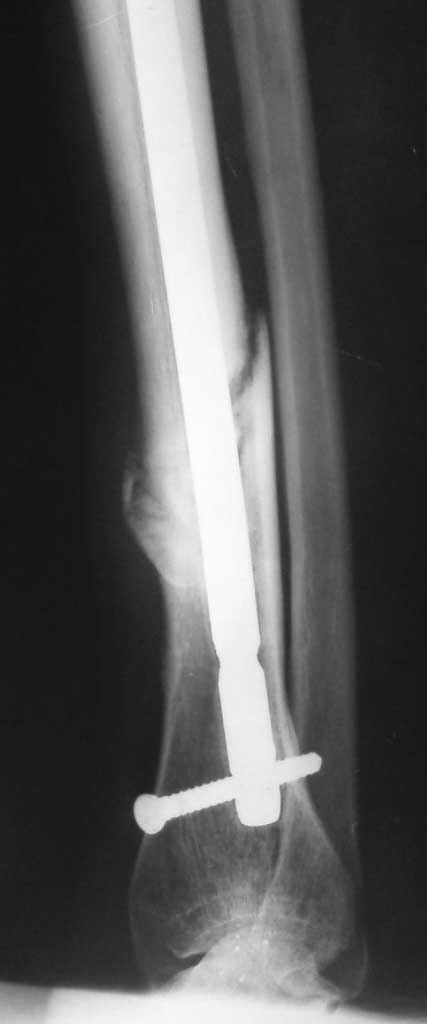

Очень интересная тема – дистальное блокирование при инфраистмальных переломах. К сожалению, аргументировано её осветить не представляется возможным в жёстких рамках поста. С моей точки зрения, неадекватное дистальное блокирование при инфраистмальных переломах большеберцовой кости является наиболее частой причиной неудач при интерлокинге. Можно ожидать проблем, если блокирование таких переломов выполняется только во фронтальной плоскости. Даже третий блокирующий винт, проведенный в сагиттальной плоскости, не всегда гарантирует необходимую стабильность (пример 1-1 – 1-3 во вложенном файле). Нестабильность фиксации случается, как правило, из-за того, что диаметр блокирующих винтов меньше диаметра блокирующих отверстий стержня, что позволяет блокирующим винтам (а значит и дистальному отломку) отклонятся от перпендикулярного положения относительно стержня. Чем больше разница в диаметрах, тем больше угол возможного отклонения. Несколько большую стабильность обеспечивают блокирующие винты, заворачивающиеся в стержень (отмечены стрелками). Мы для себя взяли за правило выполнять дистальное блокирование всех инфраистмальных переломов минимум тремя винтами, проведенными в разных плоскостях (пример 2-1 – 2-3 во вложенном файле). А с учётом того что мы не ограничиваем нагрузку в послеоперационном периоде и с целью уменьшения вероятности перелома блокирующих винтов при нагрузке - стандартная процедура дистального блокирования состоит во введении четырёх блокирующих винтов введенных в разных плоскостях (пример 3-1 – 3-2 во вложенном файле).

После применения такой методики не отмечено случаев несращения после интерлокинга инфраистмальных переломов.